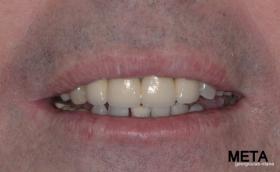

ΠΡΟΣΘΕΤΙΚΗ ΑΠΟΚΑΤΑΣΤΑΣΗ ΣΤΗΝ ΑΝΩ Κ ΚΑΤΩ ΓΝΑΘΟ ΚΑΙ ΤΟΠΟΘΕΤΗΣΗ ΕΜΦΥΤΕΥΜΑΤΩΝ ΜΕ ΚΛΕΙΣΤΗ ΑΝΥΨΩΣΗ ΙΓΜΟΡΕΙΟΥ

Ο ασθενής  προσήλθε στο ιατρείο μας θέλοντας να βελτιώσει την εμφάνιση των πρόσθιων δοντιών του και να αποκαταστήσει την υγεία κ την λειτουργία όλου του στόματος. Πραγματοποιήθηκε περιοδοντική θεραπεία κ ενδοδοντικές θεραπείες (απονευρώσεις) όπου κρίθηκε απαραίτητο και στη συνέχεια τοποθετήθηκαν 3 εμφυτεύματα, 2 δεξιά στις θέσεις του πρώτου κ δεύτερου γομφίου κ 1 αριστερά στη θέση του πρώτου προγομφίου. Κατά την  τοποθέτηση των 2 εμφυτευμάτων της δεξιάς πλευράς, πραγματοποιήθηκε κλειστή ανύψωση ιγμορείου με το σύστημα Piezotome-Intralift , τεχνική που εξασφαλίζει τη μικρότερη δυνατή επέμβαση κ τη μικρότερη μετεγχειρητική ταλαιπωρία (minimally invasive), καθώς κ αυξητικους παράγοντες PRF. Σε όλη τη διάρκεια της θεραπείας  ο ασθενής ήταν καλυμμένος τόσο αισθητικά όσο και λειτουργικά με προσωρινές μεταβατικές αποκαταστάσεις. 4 μήνες μετά την  τοποθέτηση των εμφυτευμάτων κ την οστεοενσωμάτωσή τους, ακολούθησε η τοποθέτηση των μόνιμων αποκαταστάσεων.